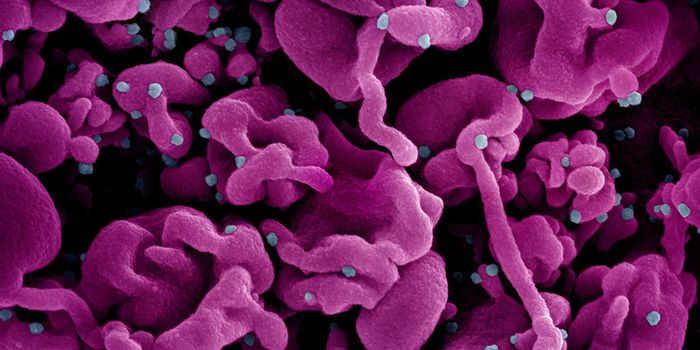

SEP 08, 2024MicrobiologySARS-CoV-2, the pandemic virus that causes COVID-19, has mutated endlessly since it burst on the scene in late 2019. An ...

AUG 27, 2024MicrobiologySince the start of the COVID-19 pandemic, the virus that causes the illness - SARS-CoV-2 - has had a practically infinit ...